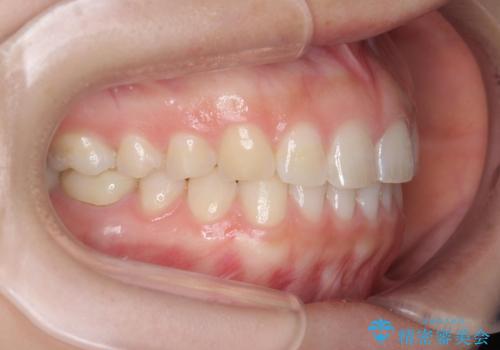

下の前歯のちょっとしたがたつきを治したい

- 下の前歯のがたつきを治したいとのことでした。

上の前歯のちょっとしたねじれも治療しています。

軽度だったため、部分矯正のコースで短期間で治療しました。

下の歯並びを並べるため、わずかに歯を削合しています。

そうしないと、前に出て上の前歯に強く当たってしまうためです。また、後戻りを防ぐ効果もあります。